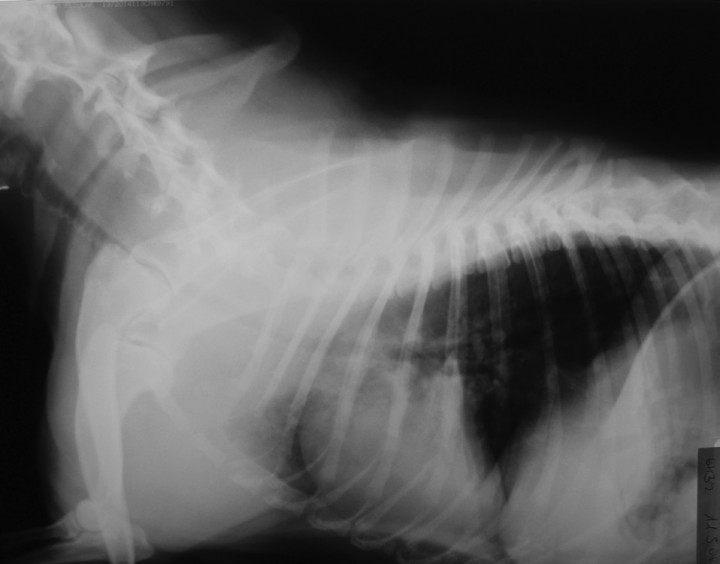

<p>Radiografía lateral del cuello y tórax. Se observa una hipoplasia de tráquea.</p>

Figura 3

Radiografía lateral del cuello y tórax. Se observa una hipoplasia de tráquea.

Hasta no hace mucho se consideraban como anomalías del síndrome braquicefálico la estenosis nasal (Fig. 1), el alargamiento del paladar blando (Fig. 2) y la hipoplasia traqueal[ https://s3.amazonaws.com/assets.prod.vetlearn.com/d0/6c96f0a41911e087120050568d3693/file/PV0511_Trappler1_CE.pdf. Consultado el 28 de enero del 2015. [PubMed] , E. Monnet. Brachycephalic airway syndrome. NAVC 2006 nov 11-15 Orlando, USA. ] (Fig. 3); sin embargo, en otros artículos[ Huck JL, Stanley BJ, Hauptman JG. Technique and outcome of nares amputation (Trader’s technique) in immature shih tzus. J Am An Hosp Assoc 2008;44(2):82-85 [PubMed] , Coyne BE, Fingland RB. Hypoplasia of the trachea in dogs: 103 cases (1974-1990). J Am Vet Med Assoc 1992 1;201(5):768-72 [PubMed] ] la hipoplasia traqueal no se considera como parte del BAS.

Radiografía de tórax

Permite diagnosticar la hipoplasia de tráquea (Fig. 3). También se realiza para detectar alteraciones pulmonares (edema de pulmón, neumonía por aspiración, etc.) o cardíacas.[ https://s3.amazonaws.com/assets.prod.vetlearn.com/d0/6c96f0a41911e087120050568d3693/file/PV0511_Trappler1_CE.pdf. Consultado el 28 de enero del 2015. [PubMed] ] Además nos es útil a la hora de elegir el tamaño del tubo endotraqueal y así minimizar el riesgo a la hora de intubar.